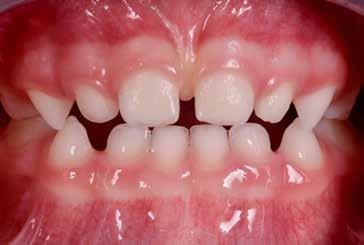

Presentazione del caso > F.V, bambino di cinque anni, presenta una malocclusione di II Classe scheletrica, III Classe dentale molare e canina destra e sinistra, morso inverso anteriore. Le arcate dentali mostrano usura degli elementi dentari anteriori a causa dell’occlusione patologica. Le linee mediane, superiore ed inferiore, sono centrate; il frenulo labiale superiore patologico per un’eccessiva estensione inter-incisale.

Dall’esame clinico si evince la III Classe dentale, l’inversione anteriore e l’over-jet negativo.

Considerazioni > L’analisi cefalometrica ad inizio trattamento dimostra la II Classe scheletrica con protrusione del mascellare superiore e prognazia mandibolare; tendenza alla crescita verticale. L’esame clinico evidenzia una protrusione mandibolare funzionale.